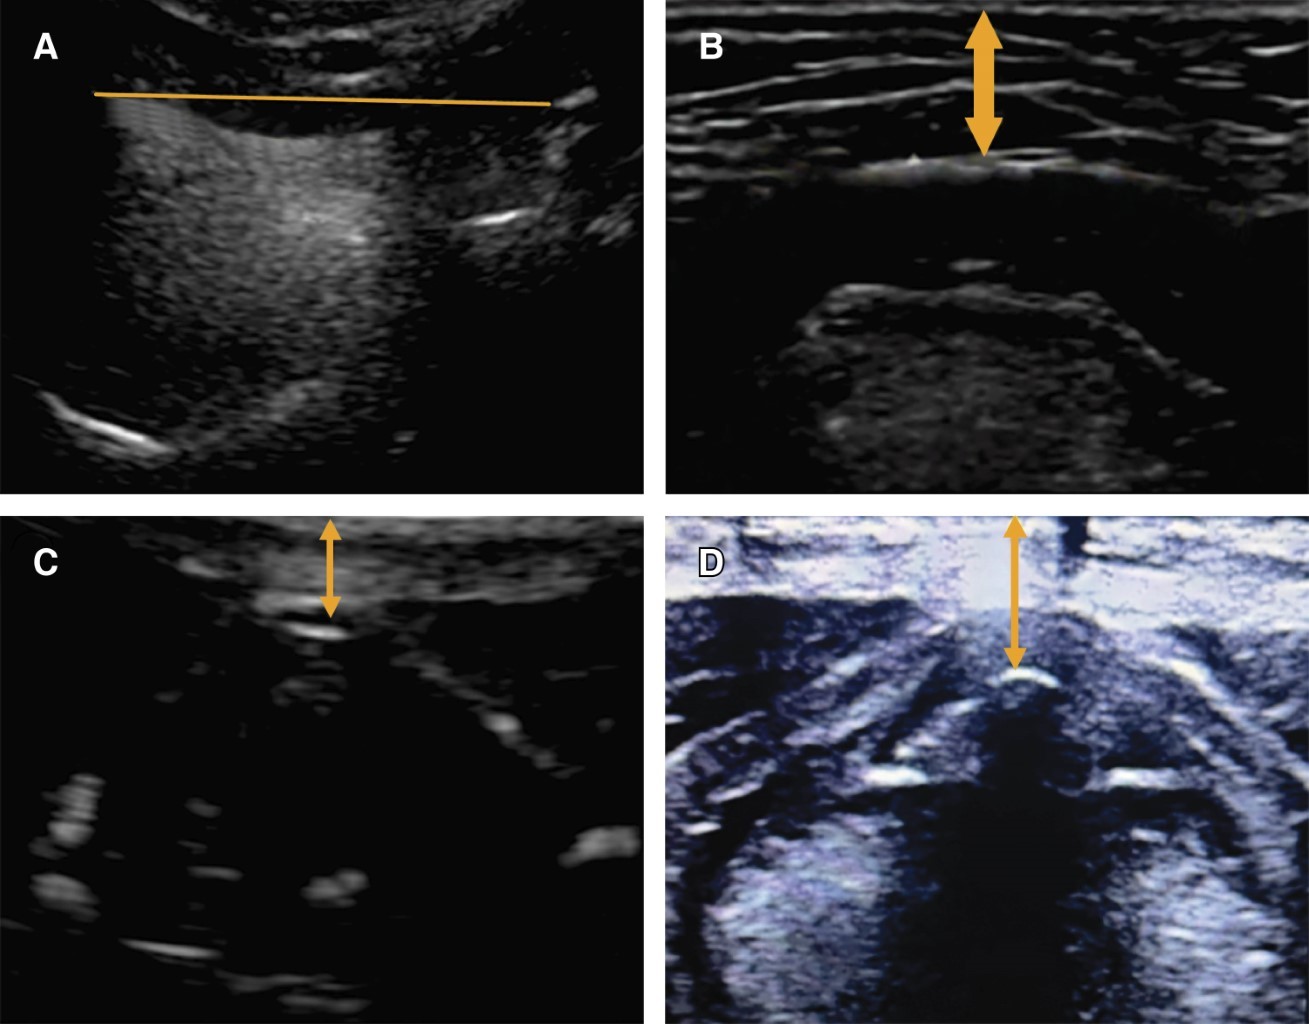

PRUEBAS ULTRASONOGRÁFICAS:

• 1. Distancia hiomental: el paciente en posición supino con cabeza y cuello en posición neutra sin almohada utilizando ecógrafo con el transductor se mide la distancia desde el borde anterior del hueso hioides hasta el borde posterior del mentón.

• 2. Distancia piel-hueso hioides: el paciente en posición supino con cabeza y cuello en posición neutra sin almohada utilizando ecógrafo con el transductor lineal, en eje corto y con una inclinación entre 30-45 grados en dirección cefálica, se realiza la medición.

• 3. Distancia piel-epiglotis: el paciente en posición supino con cabeza y cuello en posición neutra sin almohada utilizando ecógrafo con el transductor lineal, en eje corto y con una inclinación entre 30-45 grados en dirección cefálica, se realiza la ubicación de la línea media entre el hueso hioides y el cartílago tiroideo a nivel de la membrana tirohioidea con grados variables de angulación cefálica y caudal. La epiglotis se observa como una estructura discretamente móvil, por lo que se realiza la medición

• 4. Distancia piel-cuerdas vocales: se realiza en las mismas condiciones con un eje corto, a nivel de las cuerdas vocales se procede a realizar la medición de la distancia entre la comisura anterior de las cuerdas vocales y la piel (Figura 1).